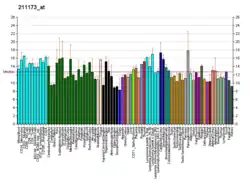

This gene encodes a G-protein coupled receptor that binds sulfated members of the cholecystokinin (CCK) family of peptide hormones. This receptor is a major physiologic mediator of pancreatic enzyme secretion and smooth muscle contraction of the gallbladder and stomach. In the central and peripheral nervous system this receptor regulates satiety and the release of beta-endorphin and dopamine.[5]